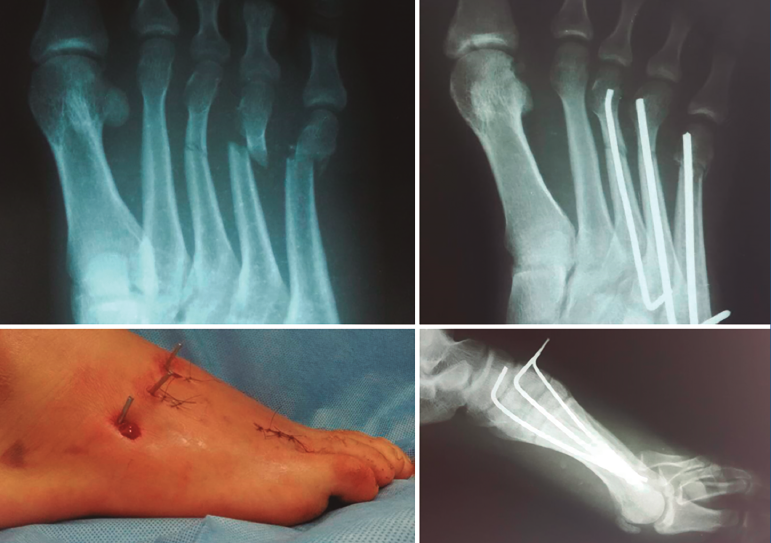

Figura 3. Sexto paciente objeto de nuestro estudio, masculino, de 21 años, que sufre fractura en 3.º, 4.º y 5.º metatarsianos por traumatismo directo en accidente de motocicleta. En sentido horario empezando arriba a la izquierda: radiografía preoperatoria, radiografías postoperatorias a la tercera semana (proyecciones anteroposterior y lateral en apoyo), aspecto del pie al finalizar el procedimiento quirúrgico.

En las Figuras 3 y 4 se presentan los resultados postoperatorios de los pacientes incluidos en nuestro estudio.